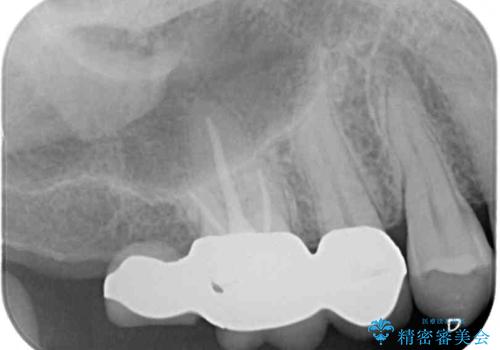

右上の一番奥の歯が欠損しており、その手前の歯2つを土台に連結されたクラウンが装着されていました。

不安定な咬み合わせとなっており、クラウンの表面が剥離していたため、インプラントによる欠損補綴治療を行い、手前2つの歯も一緒に補綴治療を行うこととしました。